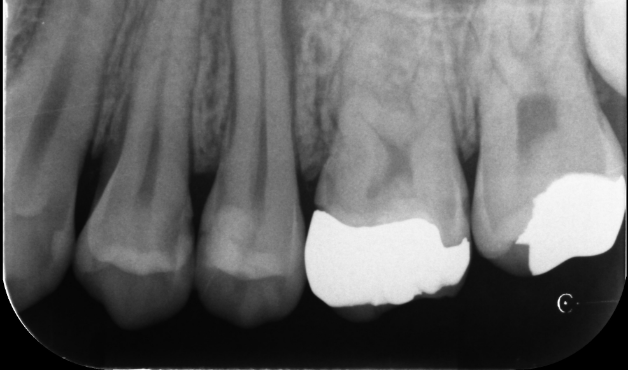

大臼歯の再根管治療を行った症例

タップで写真の拡大ができます。

Before&After(根管治療)

Before

Before&After(根管充填)

主訴

歯茎が腫れて、噛むと違和感がある

治療内容

再根管治療(大臼歯)

治療期間

1ヶ月

治療費用

165,000

治療の

リスク

処置中に歯肉縁下におよぶ重度のう蝕や破折を認めた場合、治療を中断する可能性があります。術後も症状が残る場合は追加の処置が必要になる可能性があります。